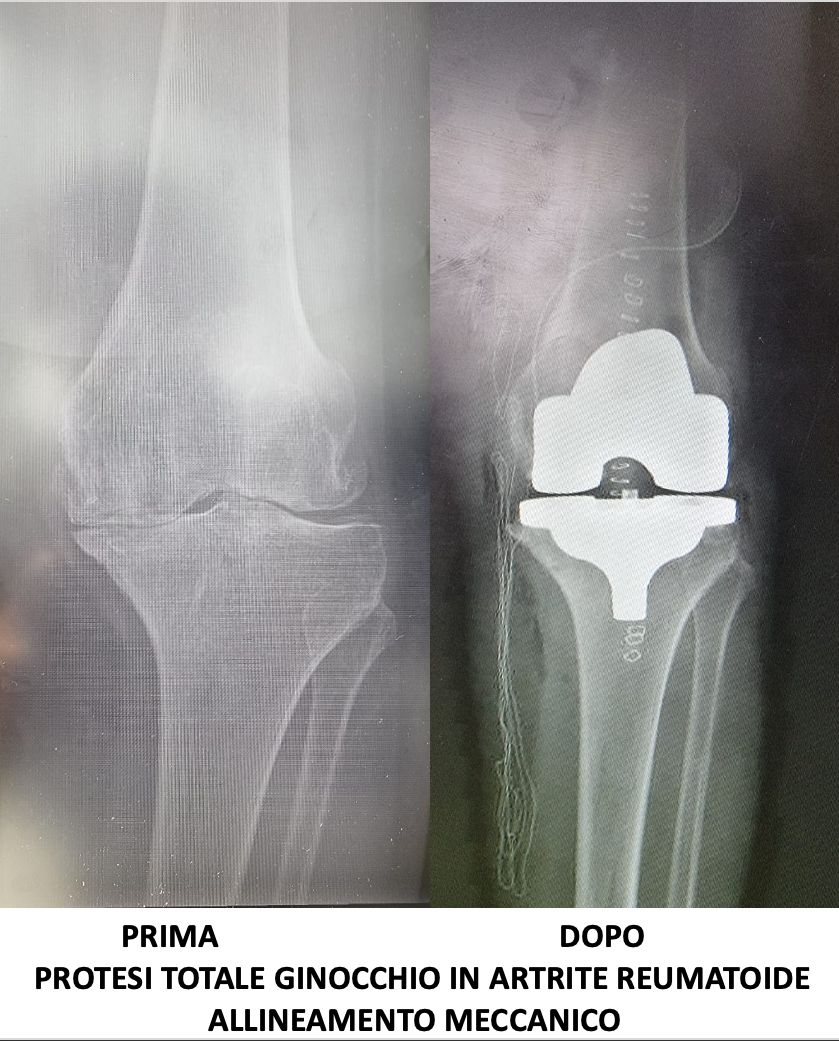

Nel 2018 frequenta come “Academic Observator” l’U.O. di Ortopedia “CDC Sileno e Anna Rizzola” di San Donà di Piave dedicandosi alla protesica di ginocchio con protocollo “fast-track”, pubblicando articolo su rivista internazionale intitolato “Experience-optimised fast track improves outcomes and decreases complications in total knee arthroplasty”.

Svolge la sua attività presso l’Ospedale del Mare, occupandosi di chirurgia traumatologica, con predilezione alla protesica di ginocchio e medicina rigenerativa della cartilagine articolare.